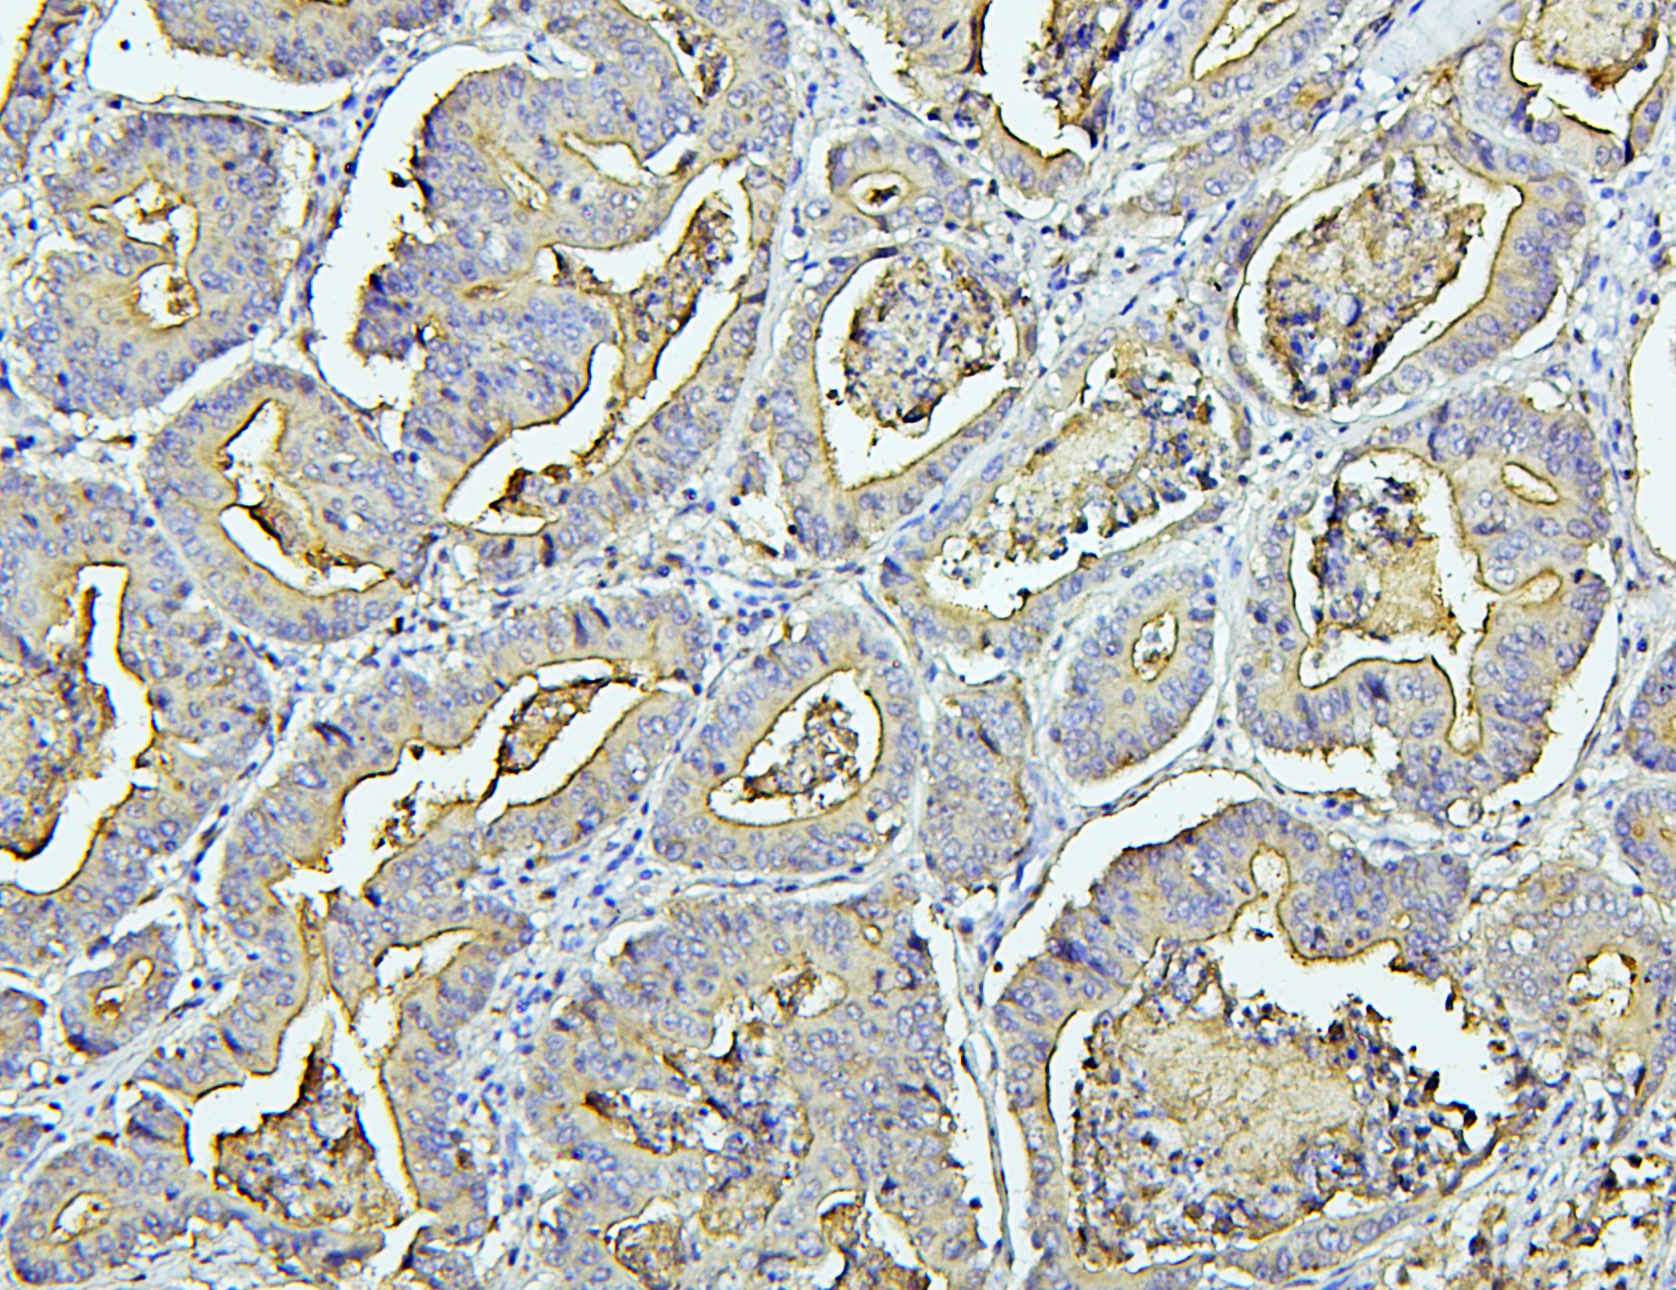

IHC analysis of CEA/CEACAM5 using anti-CEA/CEACAM5 antibody (A00356).

CEA/CEACAM5 was detected in a paraffin-embedded section of human intestinal cancer tissue. Biotinylated goat anti-rabbit IgG was used as secondary antibody. The tissue section was incubated with rabbit anti-CEA/CEACAM5 Antibody (A00356) at a dilution of 1:200 and developed using Strepavidin-Biotin-Complex (SABC) (Catalog # SA1022) with DAB (Catalog # AR1027) as the chromogen.